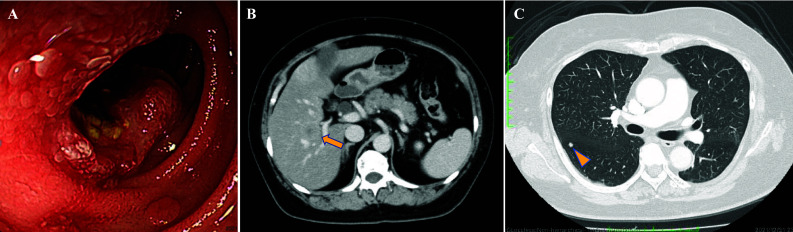

Patients with advanced duodenal carcinoma typically have a poor prognosis due to limited practical chemotherapy options. While studies on genotype-directed therapy in patients with duodenal carcinoma is progressing, clinical data assessing the efficacy of molecularly targeted therapy remains scarce. We report the case of a 65-year-old woman diagnosed with anaplastic lymphocyte kinase (ALK) fusion-positive advanced duodenal carcinoma. The patient had been treated with alectinib for approximately 2 years for ALK-positive duodenal carcinoma but developed progressive liver metastases, indicating alectinib failure. During the disease progression, circulating tumor DNA (ctDNA) sequencing revealed the emergence of ALK L1196M mutation, which demonstrated sensitivity to brigatinib. After switching to brigatinib, marked shrinkage of liver metastases was observed. The patient maintained brigatinib treatment for 7 months until tumor progression. This is the first report demonstrating the efficacy of brigatinib after alectinib failure in a patient with duodenal carcinoma harboring ALK fusion. Furthermore, this case suggests that ctDNA sequencing can detect specific acquired mutations and help expand optimal treatment options for patients.